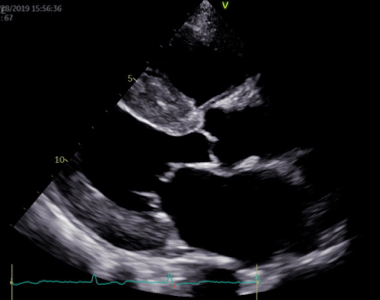

弁膜症の診断は、自覚症状が重要です。診察では、動悸・息切れ・疲れやすさなど、どの程度日常生活が制限されているかを問診します。さらに視診・触診を行って呼吸の状態や浮腫の有無を判断し、聴診により心雑音の有無と性状を確認します。弁膜症の検査は、胸部レントゲン写真・心電図・血液検査なども行いますが、なんといっても心エコー図検査は診断的価値が高いです。

心エコー図検査は体に害のない、痛みを伴わない検査です。どの弁が障害されているのかを特定し、その動きや狭窄・逆流の程度を診断します。同時に、心臓の部屋の大きさや機能を診断しますが、これらは治療方針に直結します。体に負担のない検査なので、治療後に繰り返し検査をして、どの程度改善しているかを評価することもできます。さらに、手術が必要な方には、心臓血管外科医が手術を行う際に必要となる様々な情報を提供します。

心エコー図検査